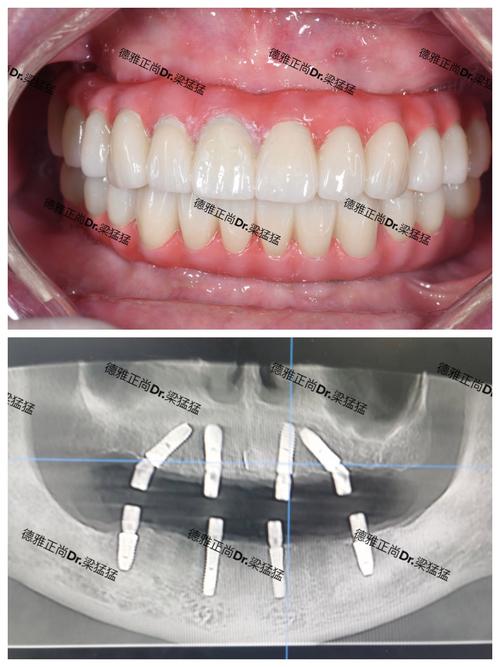

- 原理: 将一个纯钛的种植体(人工牙根)通过小手术植入到缺牙位置的牙槽骨内,等种植体与牙槽骨紧密结合(骨结合)后,在种植体上安装基台,再在基台上安装牙冠(可以是全瓷冠)。

- 美观自然: 配合全瓷牙冠,美观效果非常好,几乎可以乱真。

| 美观性 | 非常好(配合全瓷冠) | 非常好 |

- 对美观的极致要求: 两者都能达到很高美观度,种植牙配合全瓷冠更接近自然。